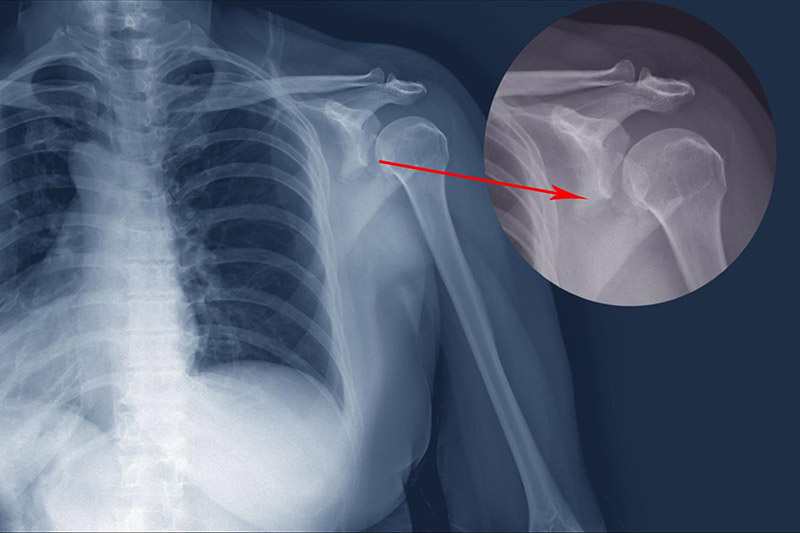

Khớp chính của vai gồm xương cánh tay, đầu xương có hình quả bóng tựa vào “ổ cắm” hình chiếc cốc ở mép xương bả vai. Viêm cũng có thể xảy ra ở khớp cùng đòn, nơi xương đòn tiếp xúc mỏm cùng vai. Về lâu dài, viêm sẽ gây tổn thương sụn, làm mất mô bao phủ đầu xương, khiến xương trượt trong khớp không còn trơn tru. Khi lớp sụn bị mất, xương trong khớp sẽ cọ xát trực tiếp vào nhau gây đau. [2]

Trật khớp vai xảy ra ở 2 dạng, trật một phần và trật hoàn toàn. Trật một phần (subluxation) là khi “bóng” của xương cánh tay lệch ra khỏi ổ cắm. Trật khớp toàn bộ xảy ra khi “bóng” hoàn toàn thoát ra khỏi ổ cắm. Khi dây chằng, gân và cơ quanh vai bị lỏng hoặc rách sẽ bị tái trật khớp, gây đau và mất ổn định khi nâng cánh tay hoặc di chuyển ra xa. Điều này làm tăng nguy cơ tiến triển bệnh viêm quanh khớp vai.

Gãy xương vai xảy ra ở 3 loại xương chính, xương đòn, xương cánh tay (phần trên), và xương bả vai. Ở người lớn tuổi, gãy xương vai là hậu quả của việc ngã từ trên cao xuống. Người trẻ gãy xương vai do các chấn thương mạnh như va chạm khi lái phương tiện giao thông hoặc chơi thể thao. Người bị gãy xương xuất hiện cơn đau dữ dội, sưng tấy và bầm tím tại vùng vai.